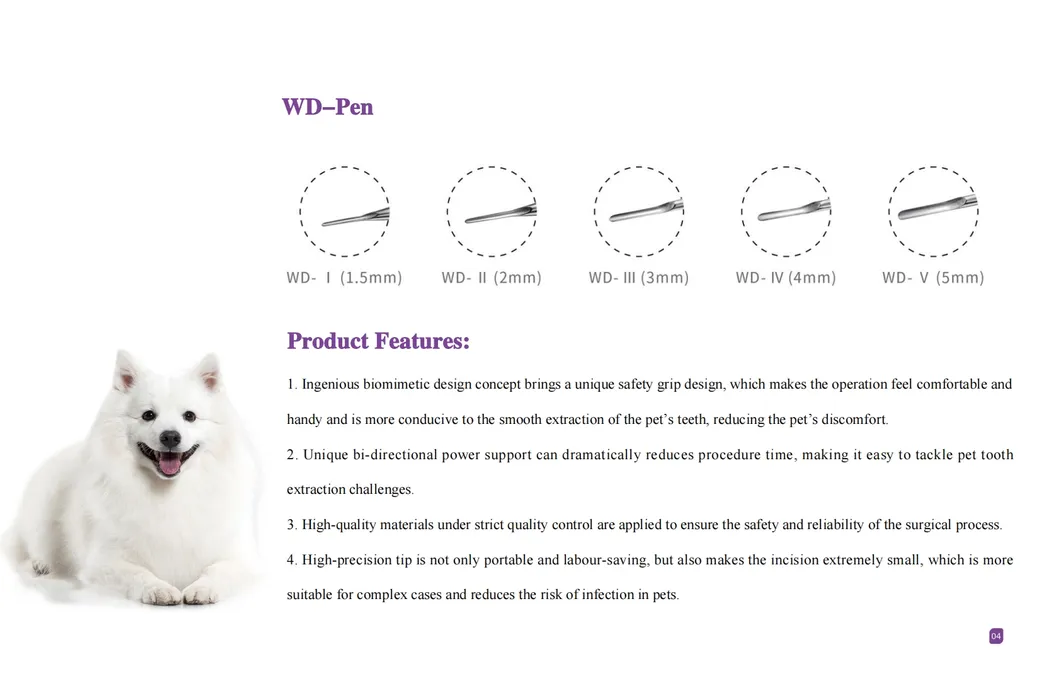

This study evaluated the effectiveness of state-of-the-art dental tools for veterinary use. The treatment group utilized the revolutionary Pneumatic Dental Elevator Kit. Critical factors observed included physiological parameters, intraoperative complications, extraction duration, and socket damage. Rigorous statistical analysis highlights the superior performance of these advanced tools.